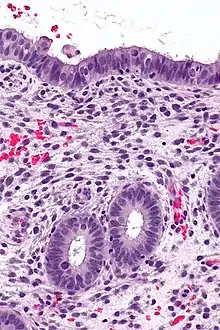

![]() | Amoebiasis | Colonic biopsy showing trophozoite of Entamoeba Histolytica with ingested red blood cells. | Category: Histopathology of amoebiasis | Amoebiasis |